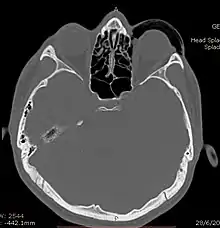

Computed tomography (CT)

Computed tomography is effective and sensitive in the diagnosis of orbital emphysema,[3][37] as it can confirm the anatomical location and size of air, bony defects, indentation of the eyeball, and the condition of the optic nerve, as well as the presence of any extraocular muscle entrapment and herniation of preorbital fat into the sinus cavities.[3][15][38] The location of the orbital emphysema is present near the site of the fracture.[1][3] The scans are usually taken along the transverse plane. Transverse images allow the evaluation of fractures in medial and lateral orbital walls. By reformatting these transverse images or taking coronal images, the examination of orbital floor and roof is permitted. Helical scanning is preferred as it has a lower imaging time and radiation dose comparing to conventional scanning, especially when reforming transverse helical scans into coronal images.[3] The staging of orbital emphysema can then be determined with visual acuity examination and ophthalmoscopy.[6] A disadvantage of using a CT scan is that when detecting air after orbital trauma, the presence of a wooden foreign object can give a false positive result of orbital emphysema. The wooden object can mimic the presence of orbital emphysema. Therefore, patients’ medical history is crucial in making the correct diagnosis.[3]